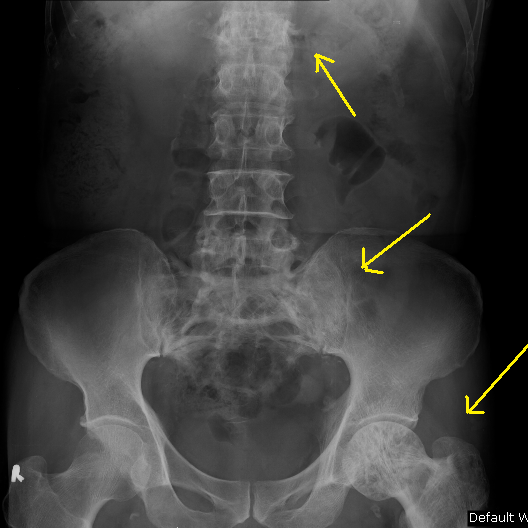

From orthopaedicprinciples.com

Paget’s Disease of Spine — Paget's Disease Medical Definition Web paget's disease of bone is a condition that causes bone breakdown, enlargement and deformities. Web paget disease of the bone is a chronic bone disorder. It can cause pain, deformity,. Bone may become dense, but fragile, because of. Web paget’s disease is a chronic disorder that affects the bones and causes them to grow larger and weaker than. Web. Paget's Disease Medical Definition.